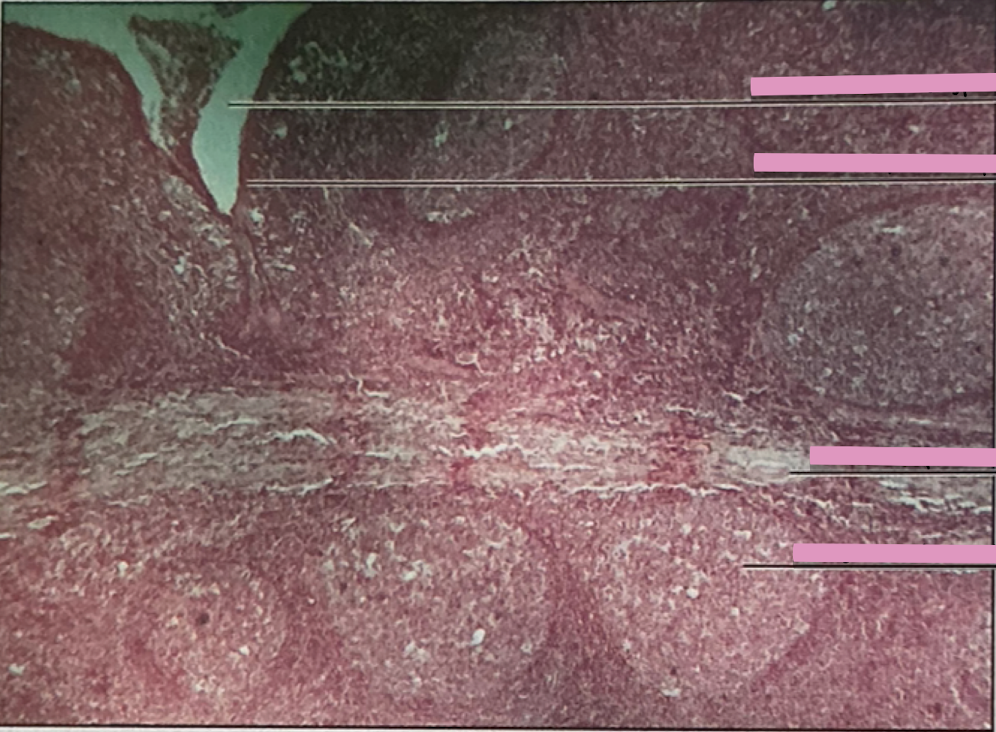

spleen

spleen

macrophages. lymphocytes, entrapment/destroy old RBCs and platelets

hodgkin’s granuloma

hodgkin’s granuloma

cancer of lymph system - breakdown of red and white pulp

reed-sternberg cells

derived from B lymphocytes